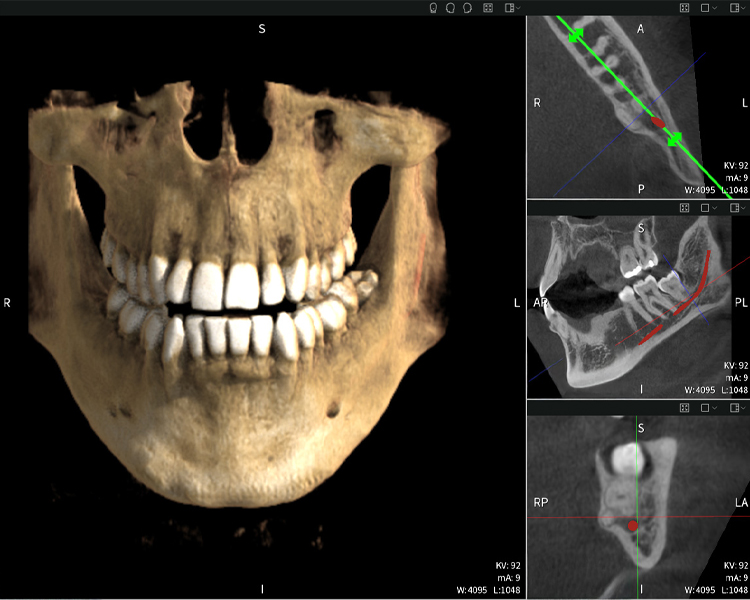

Nachstehend finden Sie einen Fall von Dr. med. dent. Oliver A. Centrella, in dem die CBCT-Aufnahmen mit Seethrough Max entscheidende Informationen zur komplexen Anatomie sowie zur kritischen Beziehung zwischen den Weisheitszähnen und dem Nervus alveolaris inferior lieferten. Bei diesem Fall besteht eine Indikation zur chirurgischen Entfernung der Weisheitszähne.

Abbildung a

- Oben links: Axiale Schnittansicht des linken Unterkiefers (Region 38) mit Darstellung des Nervus alveolaris inferior (rot) in unmittelbarer Nähe zu den Wurzeln des Zahns 38.

- Oben rechts: 3D-Rekonstruktion des gesamten Unterkiefers zur Orientierung. Der rot markierte Nervus alveolaris inferior verdeutlicht seine Lage im Kieferknochen.

- Unten links: Sagittale Ansicht des Unterkiefers (Region 38), die die enge räumliche Beziehung zwischen den Wurzeln und dem Nervenkanal verdeutlicht.

- Unten rechts: Koronale Ansicht des Unterkiefers (Region 38) entscheidend für die Beurteilung der räumlichen Lage der Wurzeln zum Nerven.

Abbildungen b–d zeigen verschiedene Ansichten einer 3D-Rekonstruktion des Unterkiefers und bieten eine umfassende Übersicht über die Anatomie des Unterkiefers, die Lage der Nerven im Verhältnis zu den Zähnen und ermöglichen die Beurteilung der Zahnsymmetrie und Ausrichtung.

Abbildung d zeigt den bereits vorbehandelte Zahn 48, dessen Krone entfernt wurde und dessen Wurzeln nahe am Nerv belassen wurden, was das hohe Risiko einer Nervenschädigung verdeutlicht.

Abbildung e: Panoramaröntgenaufnahme dient der initialen Beurteilung und zeigt die allgemeine Zahnstellung sowie mögliche pathologische Veränderungen auf. Insbesondere ist auf der rechten Seite (Zahn 48) die Situation nach einer Kronenamputation durch einen externen Behandler ersichtlich. Die beiden stark gekrümmten Wurzeln verbleiben in enger topographischer Beziehung zum Nervus alveolaris inferior im Knochen. Dies deutet auf eine bewusste Entscheidung zur Vermeidung eines erhöhten Risikos einer Nervenläsion während einer vollständigen Extraktion hin und stellt einen klinisch relevanten Befund dar. Zusammenfassend liefern die CBCT-Aufnahmen mit Seethrough Max entscheidende Informationen über die komplexe Anatomie und die kritische Beziehung zwischen den Weisheitszähnen und dem Nervus alveolaris inferior. Diese detaillierte präoperative Diagnostik ist unerlässlich für die sichere und erfolgreiche Durchführung chirurgischer Eingriffe im Unterkieferbereich.